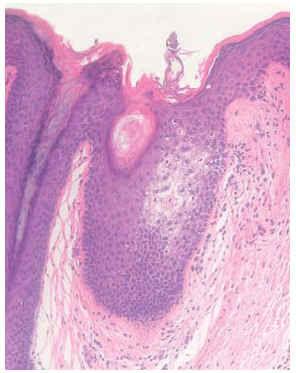

Una mujer de 16 años de edad, sin antecedentes familiares ni personales de interés, que consultó por presentar, desde hacía aproximadamente 3 meses, lesiones papulosas hiperqueratósicas perifoliculares, de 1-2 mm de diámetro, en axilas, formando placas de límites bien definidos, de forma bilateral y simétrica (fig. 1). Estas lesiones eran levemente pruriginosas. Se observaba una disminución del vello axilar. Existían también lesiones similares menos llamativas en areolas mamarias y región púbica. Se realizó biopsia cutánea de las lesiones axilares, que mostró espongiosis en el punto de entrada de la glándula apocrina en el epitelio infundibular, coincidiendo con un tapón córneo suprayacente, y un ligero infiltrado inflamatorio perifolicular (figs. 2 y 3). No presentaba ningún trastorno en las hormonas sexuales ni estaba tomando anticonceptivos orales. Dada la escasa sintomatología, se mantuvo una actitud conservadora y se pautó corticoterapia tópica en caso de cursar con prurito.

Fig. 3.--Espongiosis en el punto de entrada de la glándula apocrina en el epitelio infundibular, que coincide con un tapón córneo suprayacente, y un ligero infiltrado inflamatorio perifolicular. (Hematoxilina-eosina ×100.)

El diagnóstico de este trastorno se basa en la sospecha clínica y se confirma mediante biopsia. Histopatológicamente, los hallazgos típicos consisten en hiperqueratosis ortoqueratósica del conducto excretor apocrino intradérmico, con obstrucción del orificio de salida por tapones ortoqueratósicos, que se acompañan de un infiltrado inflamatorio perifolicular, predominantemente formado por linfocitos. Puede verse dilatación de la glándula apocrina, acantosis epidérmica y espongiosis en la pared del infundíbulo folicular. Este último hallazgo se ha considerado como específico en el diagnóstico5,6. Se ha propuesto la realización de cortes transversos seriados de las piezas de biopsia para asegurar el diagnóstico5, ya que en ocasiones en el examen anatomopatológico convencional con cortes verticales pueden no encontrarse los hallazgos característicos de este trastorno.